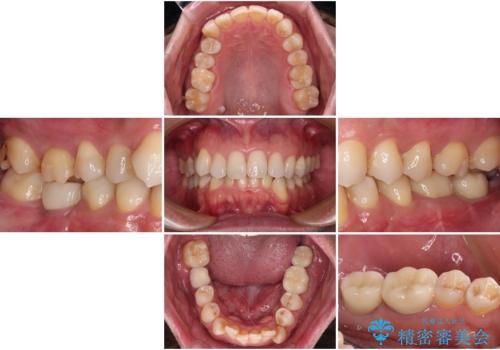

インプラントにはストローマン社のSLActiveを使用し、埋入から補綴までおよそ3か月と、短期間で治療を進めることができました。